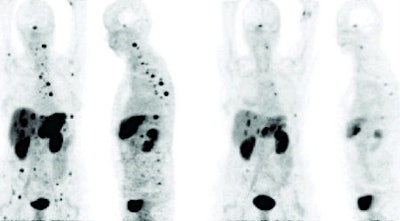

| Response to Bi-123 DOTANOC treatment observed in patients with tumors resistant to previous therapy with yttrium-90 and lutetium-177. Image above shows shrinkage of liver lesions and bone metastases after therapy with 11 GBq of Bi-123 DOTANOC. Image below shows response of multiple liver lesions after therapy with 14 GBq of Bi-123 DOTANOC. Images courtesy of SNM. |

Most importantly, the researchers observed shrinkage of the primary tumors, as well as liver and bone metastases.